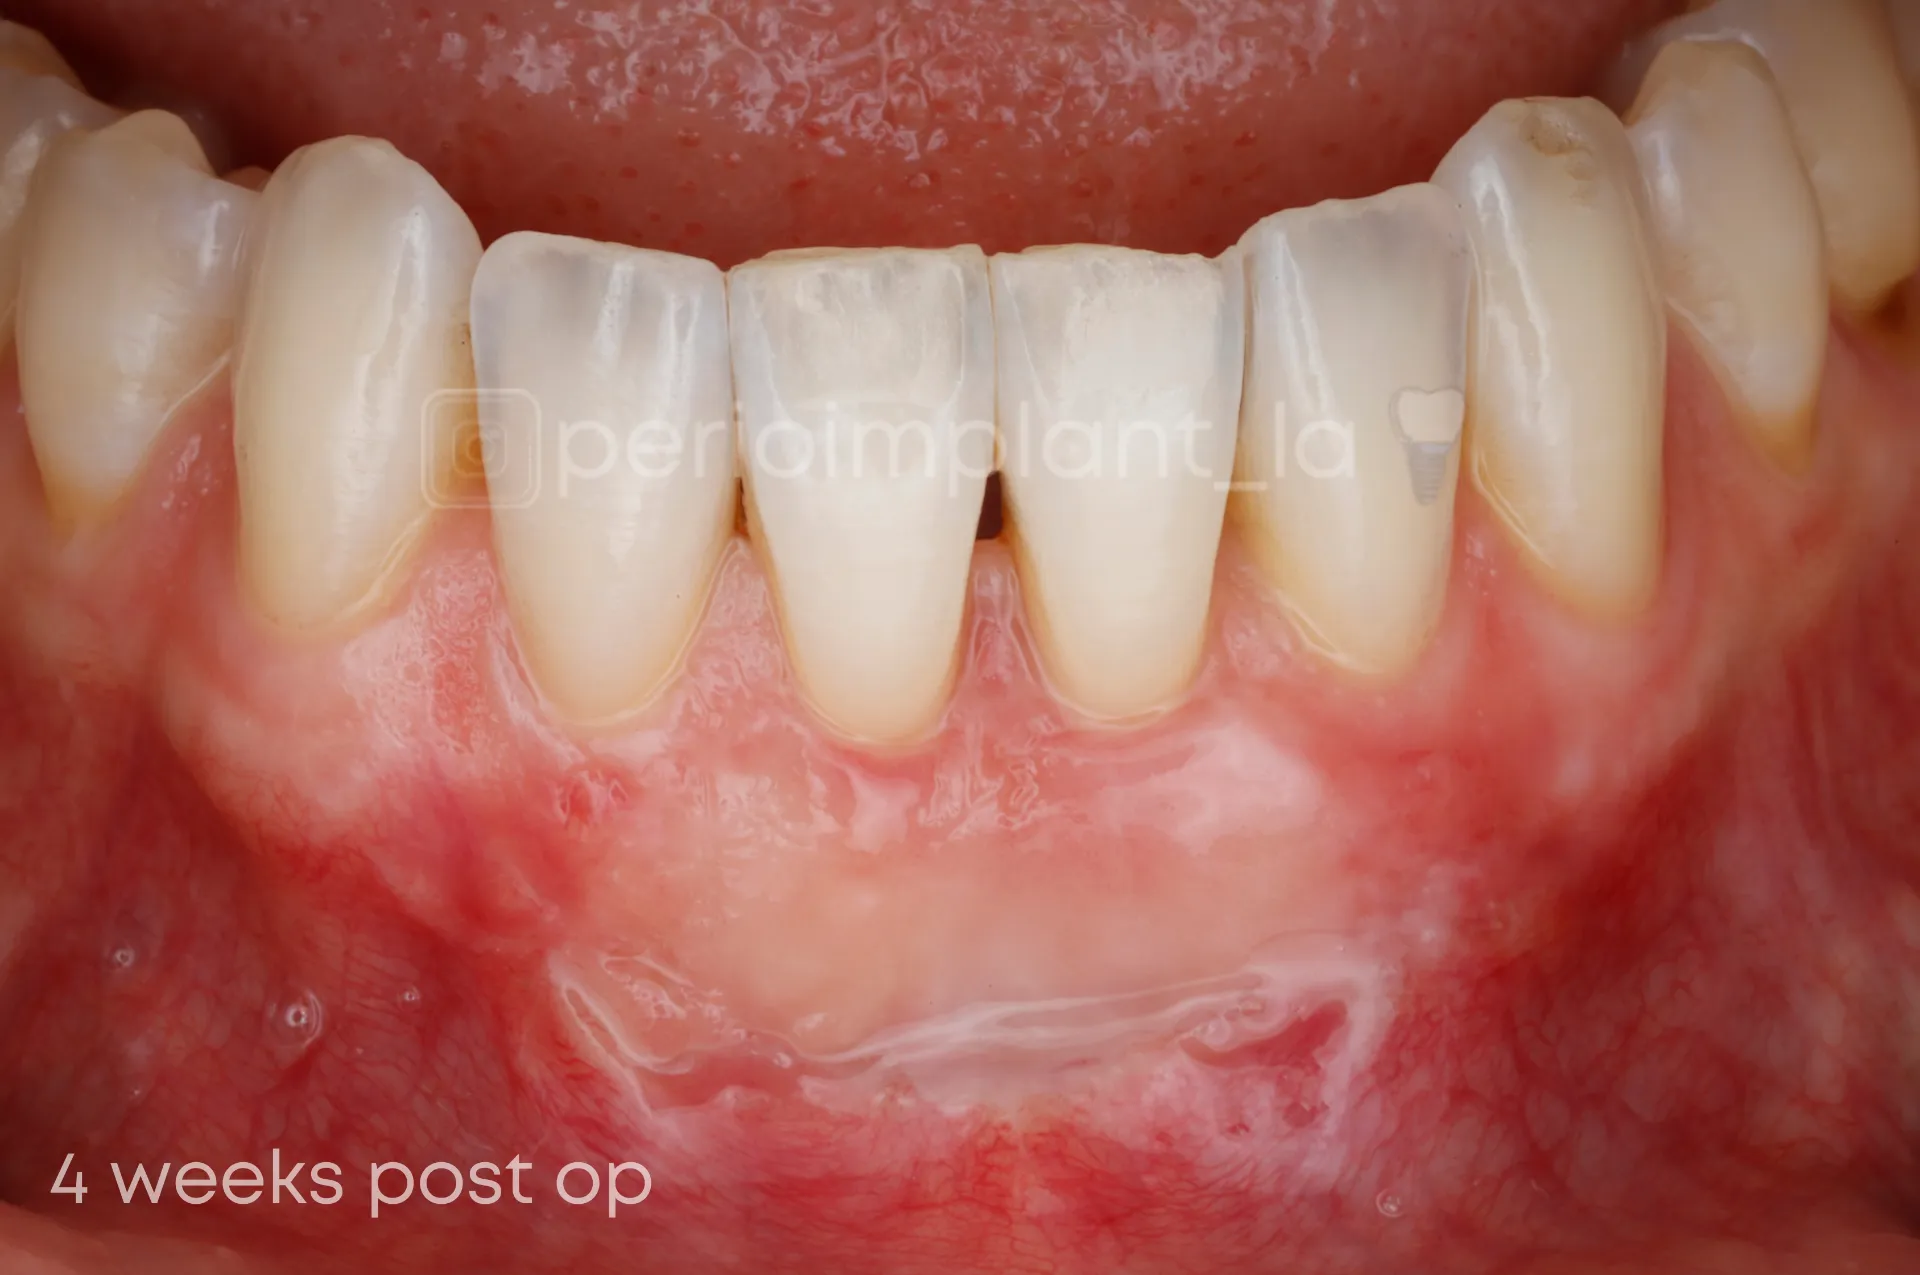

Gum Recession

Gum Grafting